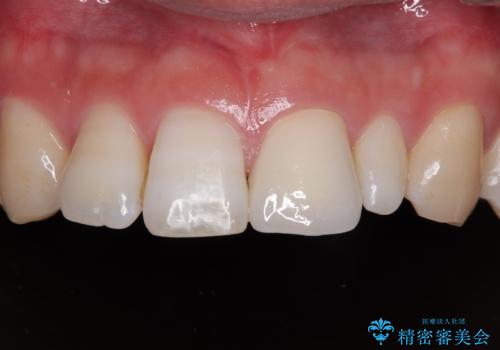

- 虫歯が多く、セラミッククラウンにより虫歯治療を行っている途中で矯正治療をしたいとのことで来院された患者様です。

上顎前歯が舌側に転位しており、なるべく早く楽に矯正したいとのことで、ワイヤー矯正を行うこととしました。

虫歯治療途中の歯は仮歯が装着されていたため、そのまま矯正治療を行い、矯正後に補綴治療を行うこととしました。